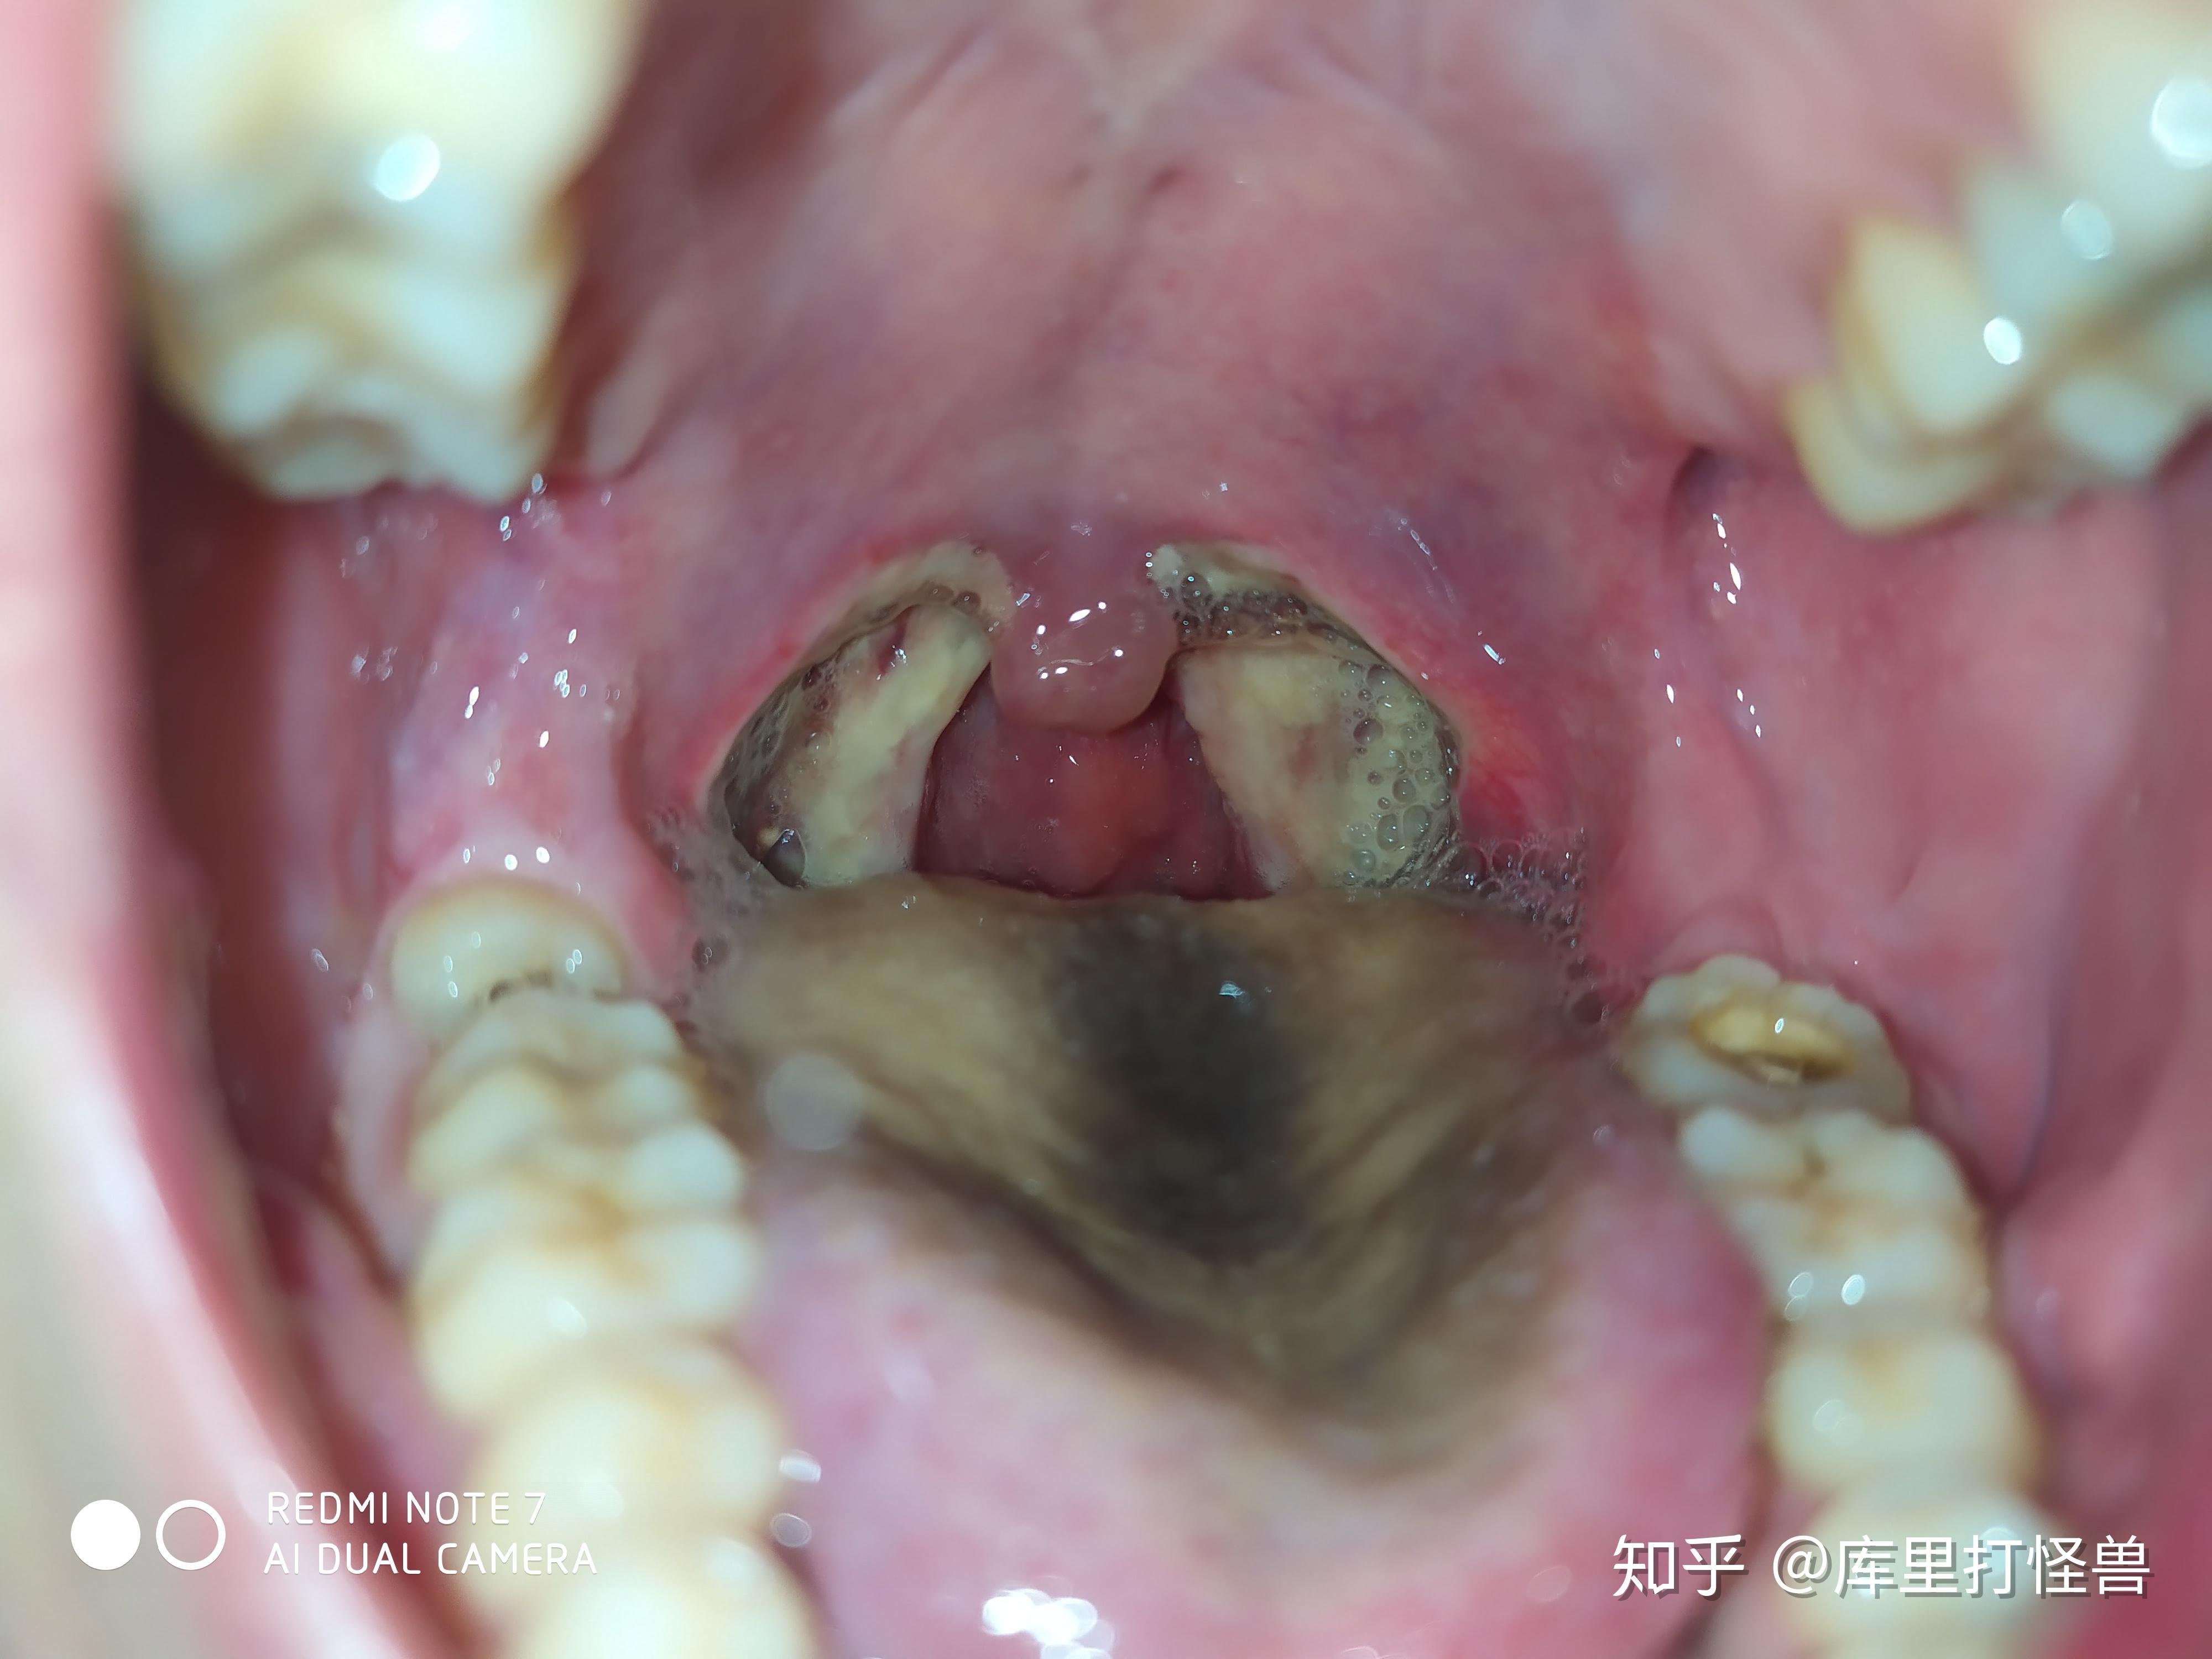

切扁桃体之后是什么感觉

图片尺寸4000x3000